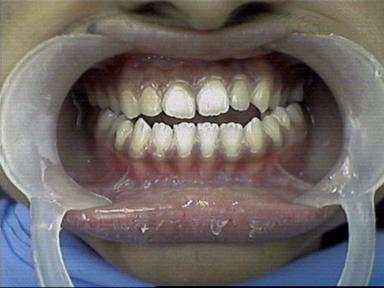

After Treatment Intra Oral